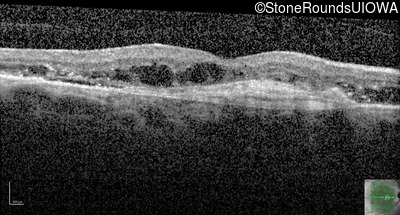

AR Stargardt Disease (IIA)

Age at visit: 59 years (Visit 3)

This 59 year old woman first noticed vision loss in her right eye a few months earlier. She has a cousin with Rhodopsin-associated RP.

Diagnosis & molecular findings

Disease Gene Allele 1 variant(s) Allele 2 variant(s) Inheritance mode

AR Stargardt Disease ABCA4 Arg219Thr AGA>ACA Gly863Ala (G)GA>(G)CA AR